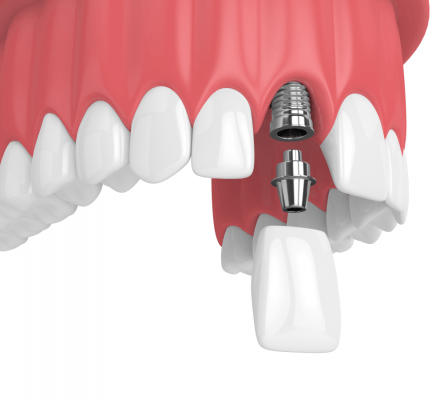

Sau khi ghép xương răng, bạn có thể đến DDS Dental để cấy ghép răng Implant.

Tại Nha Khoa DDS , bạn sẽ được đội ngũ nhân viên, bác sĩ tư vấn nhiệt tình, tỉ mỉ để tìm ra phương pháp cũng như chế độ cấy ghép implant phù hợp nhất với mình. Với DDS, chất lượng phục vụ khách hàng là trên hết, đem đến khách hàng kết quả hoàn mỹ nhất là điều chúng tôi hướng đến.